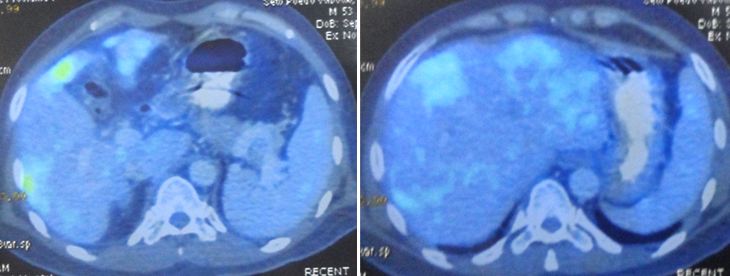

About two months later (Jun 2019), a PET scan was done. The result showed the cancer had recurred at the previous operation site. There was NO spread to the liver, lung, lymph nodes or bone.

About five months later, in November 2019, another PET was done. The results were disappointing.

- The doctor suspected the cancer had spread to the liver.

- Metabolic activity of the recurrent mass in the colon was less intense but the cancer did not go away.

- PET scan showed reactive lymph node.